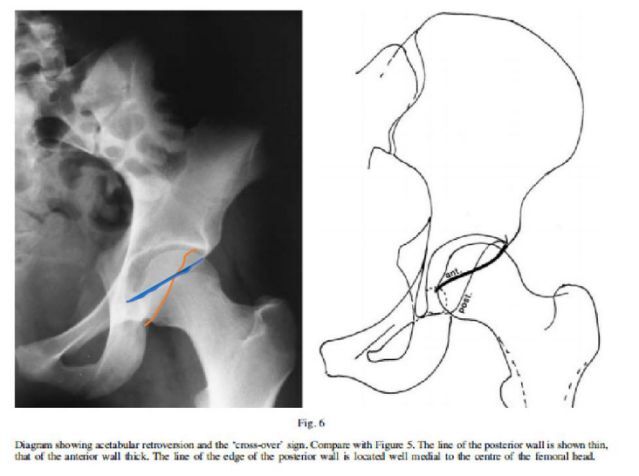

作者:北京大學(xué)人民醫(yī)院骨關(guān)節(jié)科陶可站立雙髖關(guān)節(jié)正位X線片可以看到:髖臼前緣線,髖臼后緣線;如果髖臼前緣線超過(guò)股骨頭關(guān)節(jié)面的1/3(前覆蓋過(guò)多),提示髖臼前覆蓋過(guò)大,存在髖臼前傾;如果髖臼后緣線超過(guò)股骨頭關(guān)節(jié)面的1/2(后覆蓋過(guò)多),提示髖臼后覆蓋過(guò)大,存在髖臼后傾;如果髖臼前緣線與髖臼后緣線相互交叉,稱(chēng)為交叉征陽(yáng)性(又稱(chēng)為8字征陽(yáng)性)(正常髖臼前緣線和后緣線是不交叉的)。對(duì)于髖關(guān)節(jié)撞擊綜合癥(FAI)應(yīng)仔細(xì)分型,特別需要評(píng)價(jià)髖臼后傾程度及臼頭覆蓋率。嚴(yán)重的后傾伴有后覆蓋不全,包括交叉征陽(yáng)性及后壁征陽(yáng)性,最佳治療選擇可能是髖臼周?chē)毓?,同時(shí)大多數(shù)病人還需要行股骨頭頸的矯形糾正異常前傾角。交叉征陽(yáng)性而后壁征陰性表明髖臼后壁覆蓋正常,病因主要為髖臼前上部的過(guò)度覆蓋,通常采用髖臼緣切除,術(shù)中盂唇需要切開(kāi)及再固定。